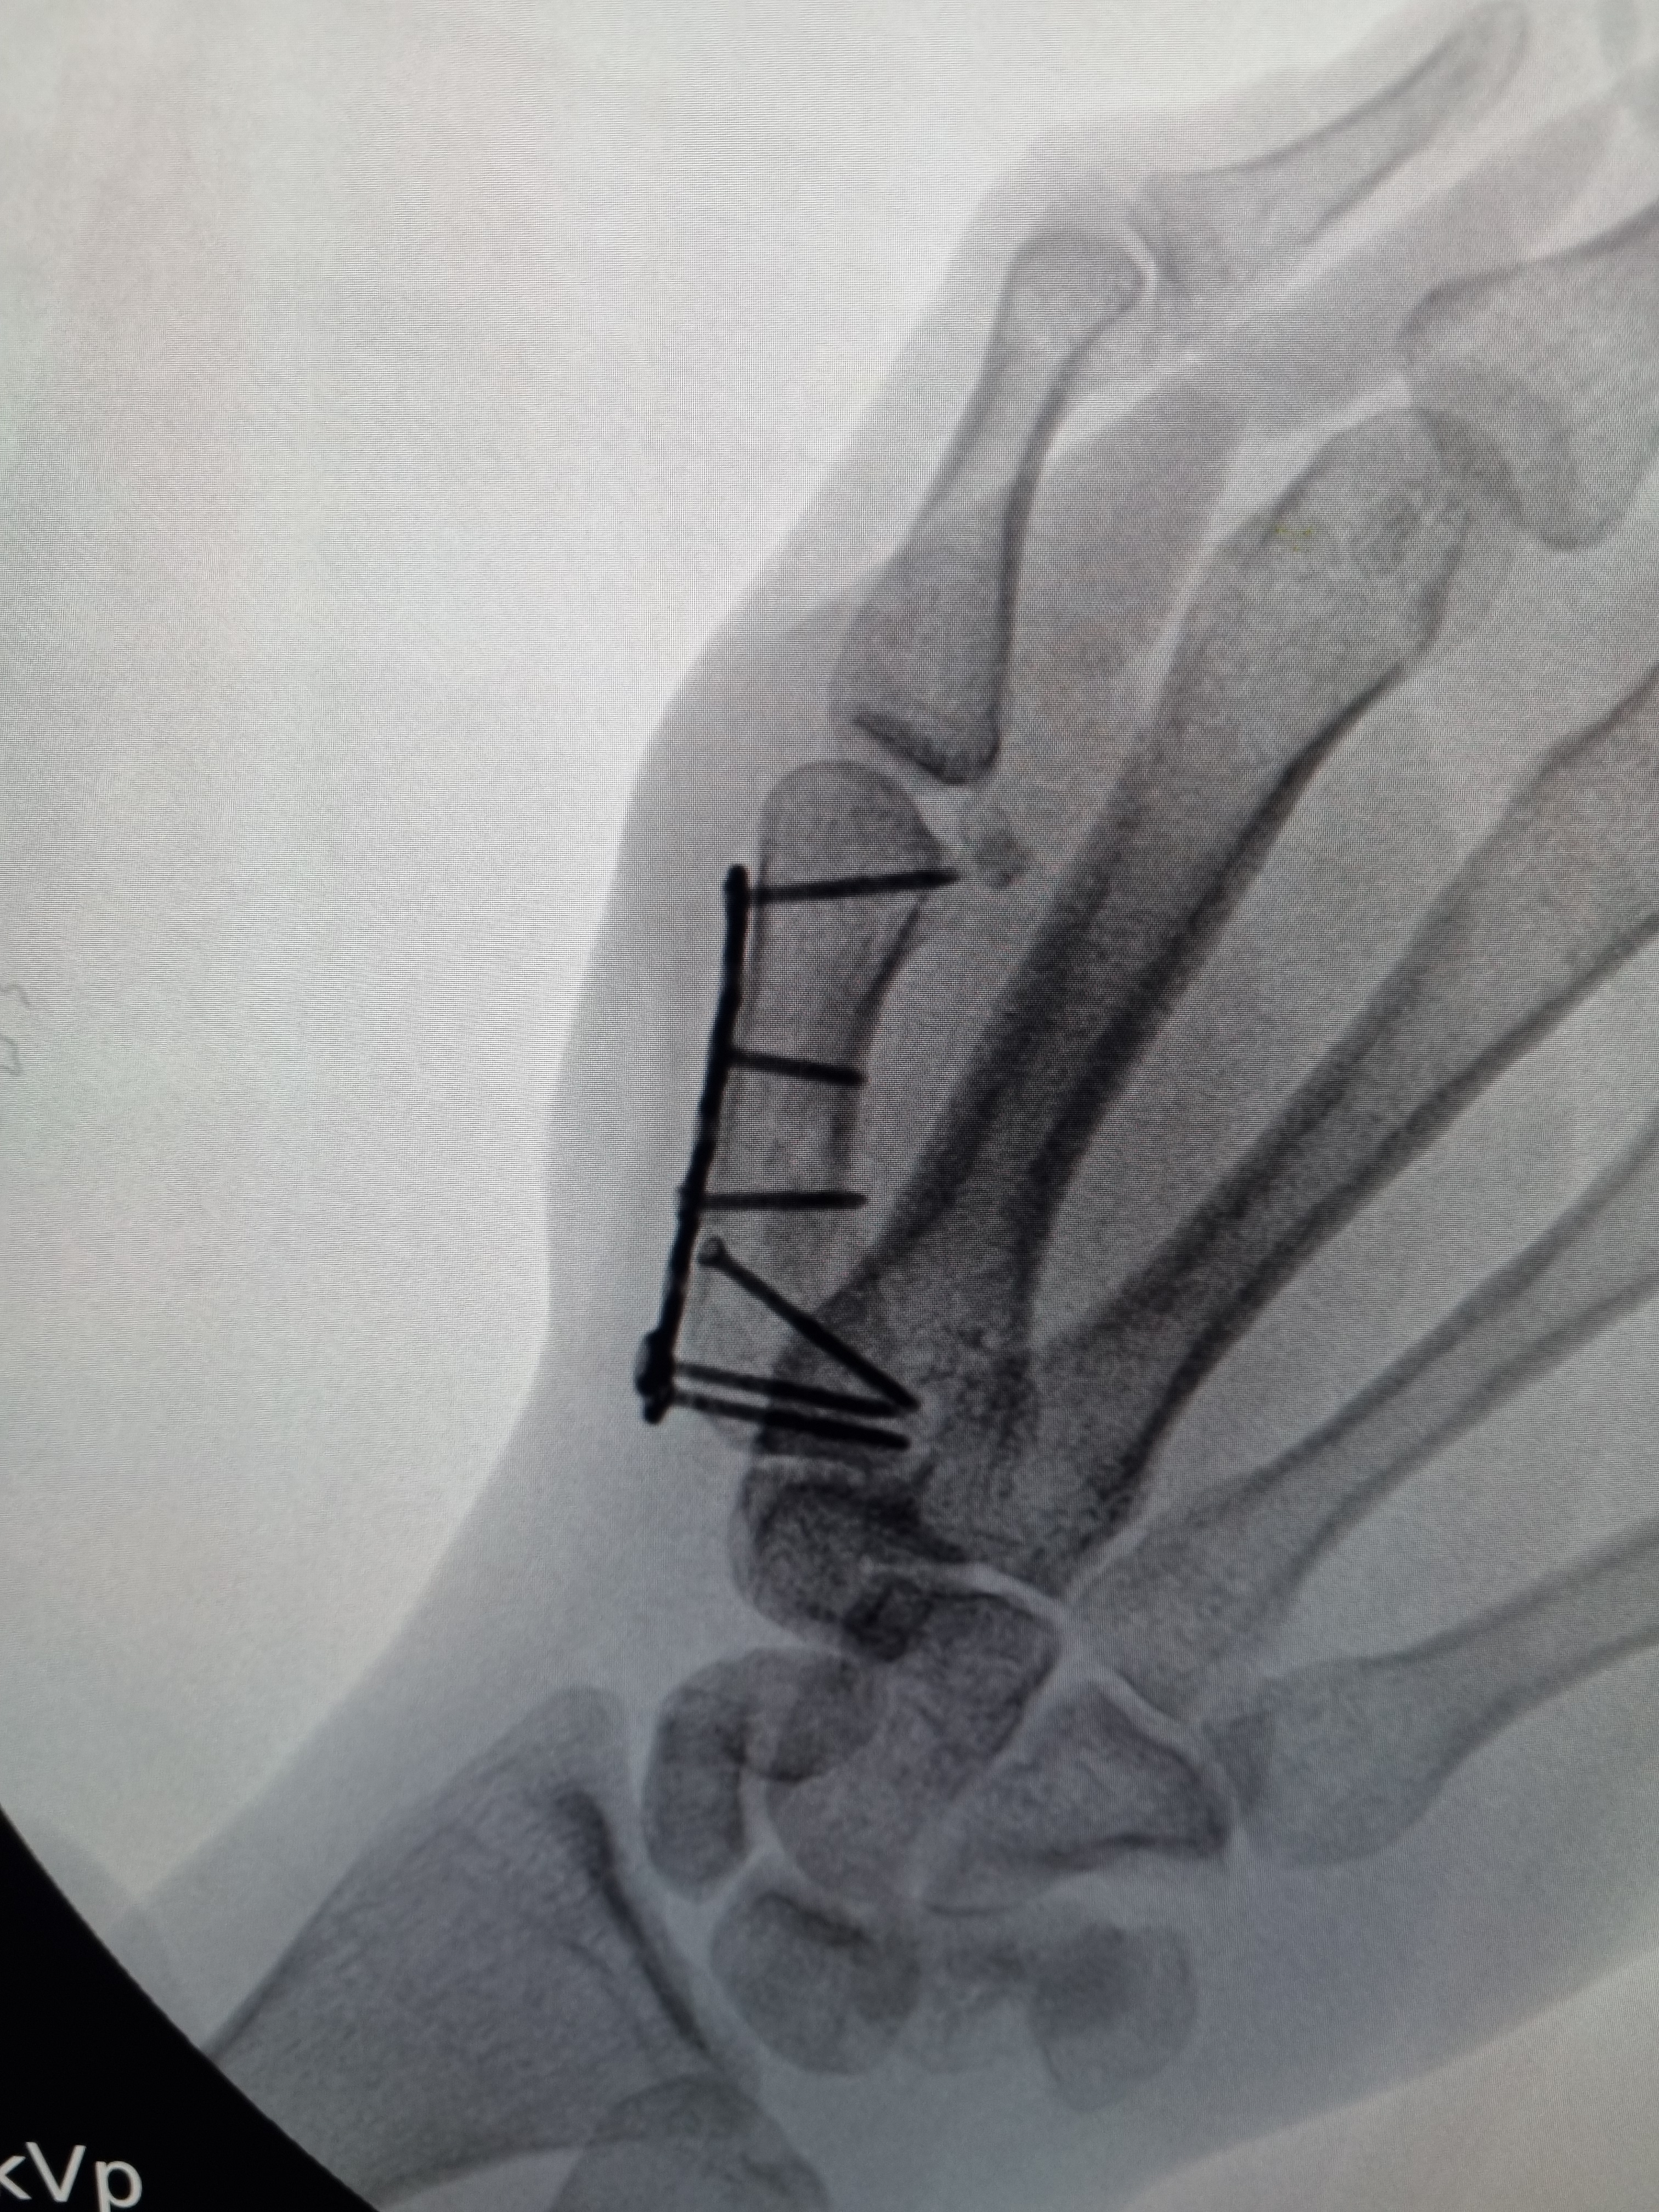

No caso de fraturas instáveis, ou com alta probabilidade de instabilidade, deve-se optar pelo tratamento cirúrgico, a fim de aumentar as chance de consolidação do osso em uma posição mais próxima do ideal possível. Para esse fim, utiliza-se materiais de síntese, as famosas placas e parafusos.

Exemplo de fratura da extremidade distal do rádio tratado com placa e parafusos